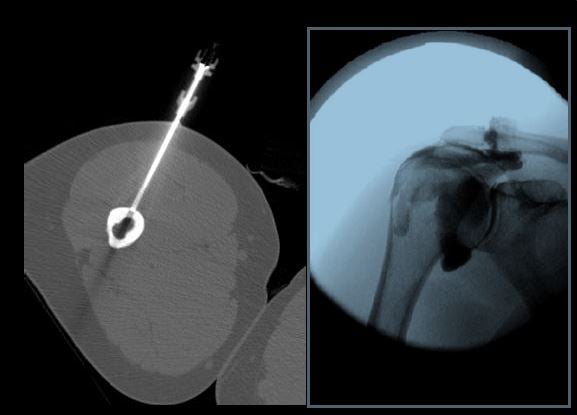

- To train fellows to become skilled in the selection, performance and interpretation of image guided intervention including fluoroscopy, CT and ultrasound guided musculoskeletal therapeutic procedures including fenestrations and steroid injections.

A wide range of diagnostic services including radiography, US, CT, MRI, and arthrography are complemented by an active MSK interventional service providing diagnostic arthrography, joint injections, and bone and soft tissue biopsies.